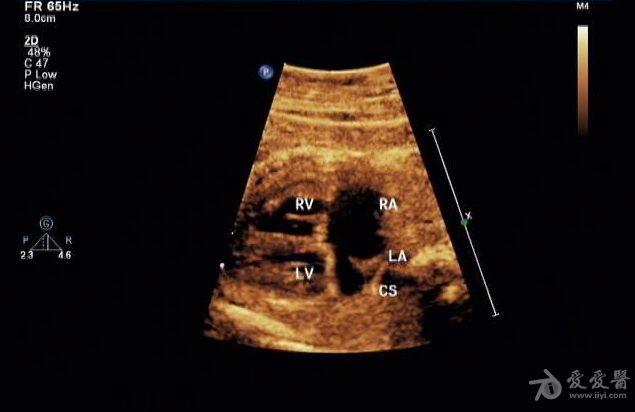

胎儿永存上腔静脉

冠状静脉窦增宽约

0.8 cm

,心底部三血管切面显示肺动脉左侧管腔样结构,频谱显示为静脉频谱。